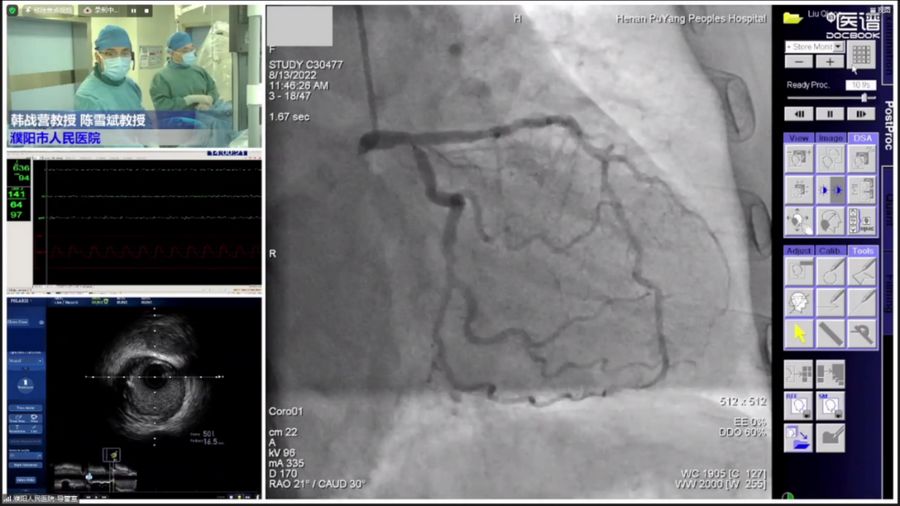

鄭州大學(xué)第一附屬醫(yī)院的韓戰(zhàn)營教授、濮陽市人民醫(yī)院的陳雪斌教授,為大家進(jìn)行了旋磨&IVUS手術(shù)演示及講解。